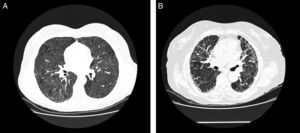

En la TCAR torácica, en las fases agudas, es característica la presencia de infiltrados difusos en vidrio deslustrado y las imágenes hiperlucentes (estas como consecuencia de bronquiolitis concomitante), que en conjunto proporcionan una imagen de perfusión en mosaico32. Es también típica la existencia de nódulos centrolobulillares en algunas de las fases de la enfermedad, pero son más frecuentes en las fases agudas32 (fig. 3A). En las formas crónicas destaca la presencia de imágenes en forma de panal. En un 20% de los casos de EPG se puede objetivar la presencia de enfisema en pacientes no fumadores33,34.

Radiología de la enfermedad del pulmón de granjero.

A. TCAR torácica de paciente con EPG aguda. Se aprecian infiltrados en vidrio deslustrado y nódulos centroacinares. B. TCAR torácica de paciente con EPG crónica. Destaca un patrón reticular en campos medios con presencia, en menor grado, de vidrio deslustrado.

La distribución de la afectación es típica en campos medios y superiores, aunque la presencia en campos inferiores no es excluyente, lo que hace en ocasiones que sea de afectación predominantemente en panal y quela imagen de la TC sea indistinguible de un patrón radiológico de neumonía intersticial usual (NIU)35 (fig. 3B).